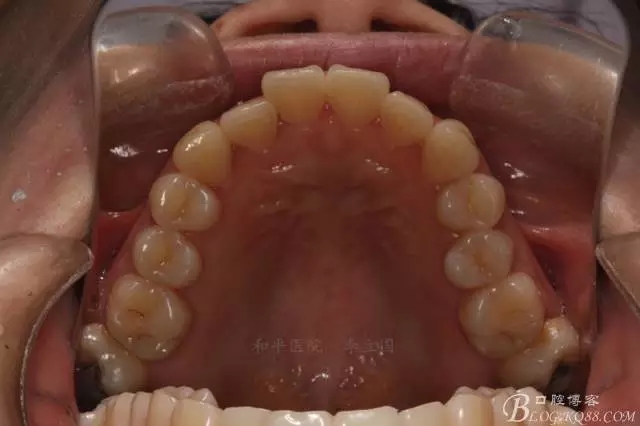

患者,女,主訴:牙齒不齊。

如圖,該病例為簡單排齊病例,但77鎖合是矯治中的關(guān)鍵所在,你會(huì)怎么處理?

該病例主要為17、27頰側(cè)位同時(shí)伴有伸長,當(dāng)然種植支抗可以解決,但還有簡單實(shí)用的辦法嗎?如圖,在橫腭桿遠(yuǎn)中延伸出牽引鉤,位置盡量遠(yuǎn)離合平面,7粘舌側(cè)扣,牽引力的方向?yàn)閴旱图吧嘞?,下圖為兩個(gè)月的效果,17已到位,27還未到位。